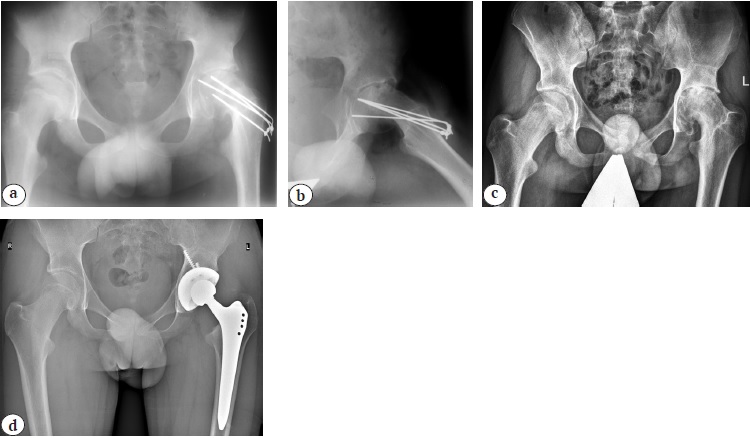

Кроме того, у 76 пациентов вне зависимости от степени тяжести дисплазии на первом году жизни применялась методика консервативного лечения по A. Lorenz. У всех этих пациентов в дальнейшем была диагностирована нестабильность тазобедренного сустава с признаками остаточной ацетабулярной дисплазии и пострепозиционного некроза головки бедренной кости в виде деформации проксимального отдела бедренной кости I–IV степеней по классификации Kalamchi – MacEwen [17], по поводу которой и были проведены хирургические вмешательства. Наиболее часто у данной категории пациентов причиной артроза являлись pincer-тип феморо-ацетабулярного импинджмента вследствие интраоперационно достигнутой гиперкоррекции вертлужной впадины во фронтальной и/или горизонтальной плоскости и значительное уменьшение угла антеверсии проксимального отдела бедренной кости при выполнения корригирующей остеотомии (рис. 6).

Рис. 6. Рентгенограммы тазобедренных суставов пациента 16 лет: a — перед проведением реконструктивного вмешательства (двусторонний диспластический подвывих бедра I степени по Crowe); b — после поэтапного выполнения корригирующей (деторсионно-варизирующей) остеотомии бедра и тройной остеотомии таза (гиперкоррекция положения вертлужной впадины, наружно-ротационное положение нижних конечностей, что может свидетельствовать о малых значениях антеверсии проксимального отдела бедренной кости); c — непосредственно перед выполнением эндопротезирования (тотальное сужение суставной щели с тотальной ретроверсией вертлужной впадины); d — среднесрочный результат тотального бесцементного эндопротезирования системой Zimmer Biomet (чашка Continuum® 50 мм; ножка Wagner cone® 15, пара трения: керамика — поперечносвязанный полиэтилен)

Fig. 6. X-ray series of the hip joints of a 16-years-old patient: a — before reconstructive intervention (Crowe I grade bilateral dysplastic hip subluxation); b — after correcting osteotomy of the femur (detorsion-varus), triple pelvic osteotomy on both sides (accompanied by hypercorrection of acetabulum positioning, external rotational position of the lower extremities, which may indicate small values of the proximal femur anteversion); с — X-ray just before THA (total joint space narrowing with total retroversion of the acetabulum); d — mid-term result of THA performed with the Zimmer Biomet system (Continuum® cup 50 mm; Wagner cone® 15, ceramic-crosslinked polyethylene)

В наше исследование вошли 34 (6,4%) пациента с последствиями перенесенной болезни Пертеса. Средний возраст пациентов на момент госпитализации составил 15,1±1,2 года. С одной стороны, отрадно, что это оказалась самая немногочисленная группа среди всех детей с ортопедическими заболеваниями тазобедренного сустава. С другой стороны, изучение данных анамнеза выявило, что 25 (73,5%) пациентов после постановки корректного диагноза получали консервативное лечение без соблюдения принципа containment therapy, т.е. в подавляющем большинстве случаев исключалась лишь осевая нагрузка на нижнюю конечность и назначался стандартный для любого ортопедического заболевания детского тазобедренного сустава комплекс восстановительной терапии, в которую входили массаж, лечебная гимнастика и такие физиотерапевтические процедуры, как электрофорез кальция на тазобедренные суставы и эуфиллина/трентала на пояснично-крестцовый отдел позвоночника. Постоянным спутником естественного течения патологического процесса в головке бедренной кости является синовит, наличие которого в совокупности с отсутствием лечения по принципу containment therapy приводит к экструзионному подвывиху с формированием грубой многоплоскостной деформации головки и вторичной деформации вертлужной впадины. Это особенно часто наблюдается у детей в возрасте старше 6 лет с субтотальным или тотальным поражением (рис. 10).

Рис. 10. Рентгенограммы тазобедренных суставов пациента 16 лет с левосторонним коксартрозом терминальной стадии, развившемся в результате БЛКП: a — перед проведением тотального эндопротезирования (асферичная головка бедренной кости с вторичной деформацией вертлужной впадины и наличием дистрофической кисты в ее своде, подвывих бедра); b — среднесрочный результат тотальной артропластики системой B. Braun Aesculap (чашка Plasmafit® 50, ножка Metha® Short Hip Stem, пара трения керамика — поперечносвязанный полиэтилен)

Fig. 10. X-ray of the hip joints of a 16-years-old patient with end-stage left-sided hip osteoarthritis as a result of LCPD: a — before THA (aspherical femoral head with secondary deformation of the acetabulum, a dystrophic cyst in its arch and hip subluxation are observed); b — mid-term result of THA performed with the B. Braun Aesculap system (Plasmafit ® 50 cup, Metha® Short Hip Stem 4, ceramic-crosslinked polyethylene)